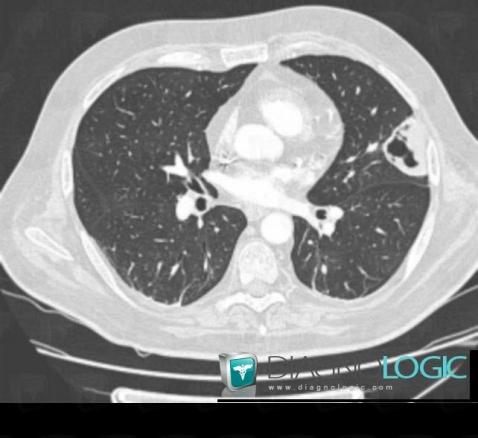

Pneumocystosis, Pulmonary parenchyma, CT

Here is the specific information in the key image above:

- Diagnosis Pneumocystosis, Location(s) Pulmonary parenchyma, with gamuts Cavitary pulmonary mass, Multiple pulmonary masses